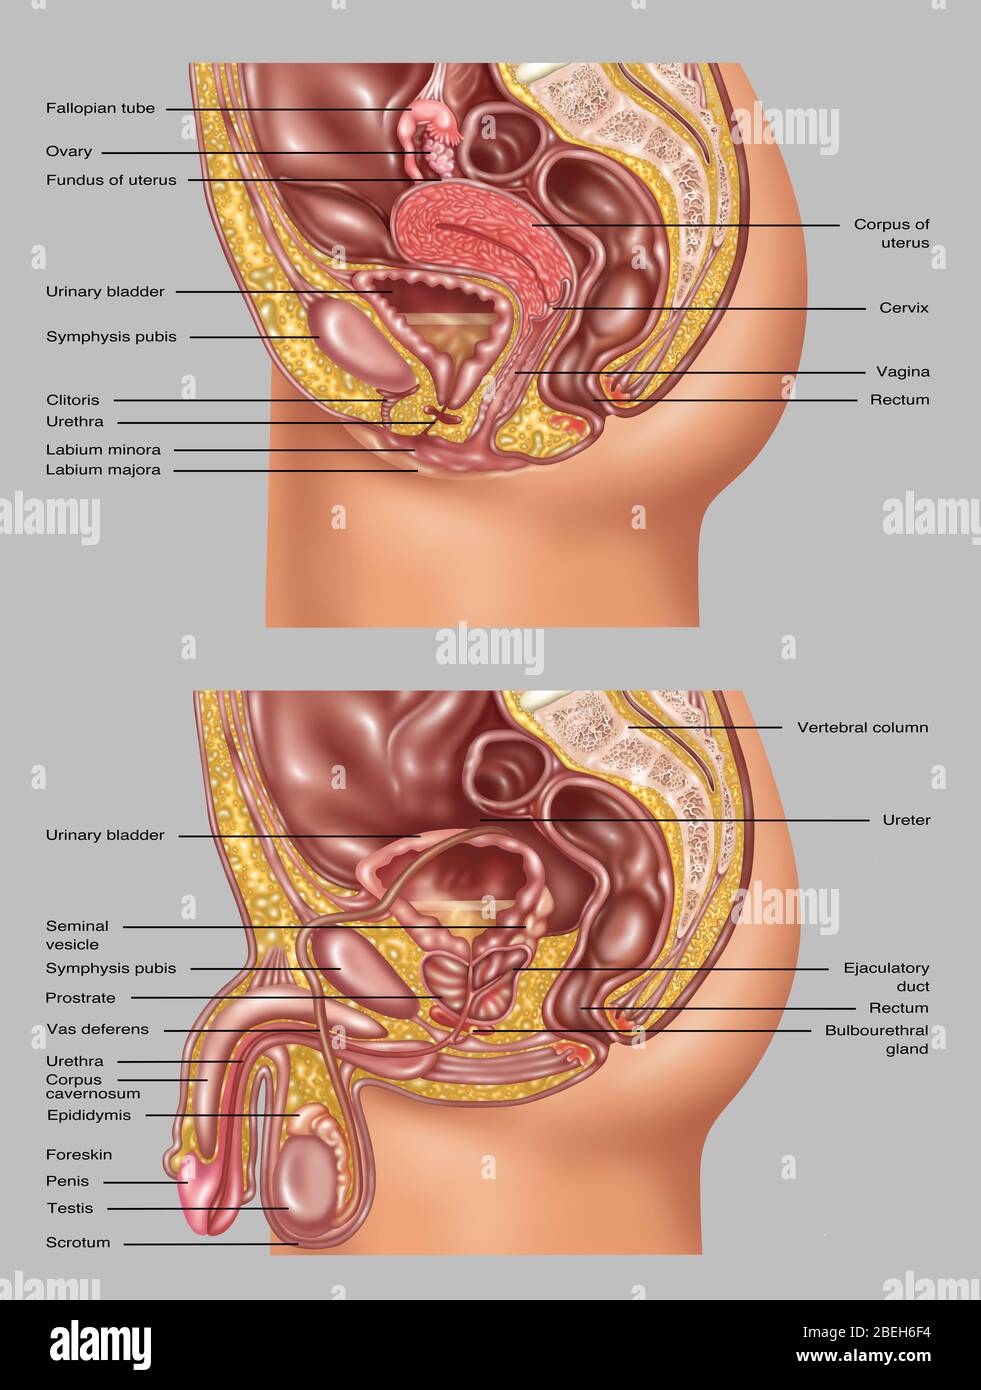

RFPAYTH0–Innere Organe, männlichen Körper - schematische Darstellung der menschlichen Anatomie Illustration - auf weißem Hintergrund.

RF2PMGJB9–Männliche Fortpflanzungssysteme auf weißem Hintergrund. Vektordarstellung männlicher Fortpflanzungssysteme